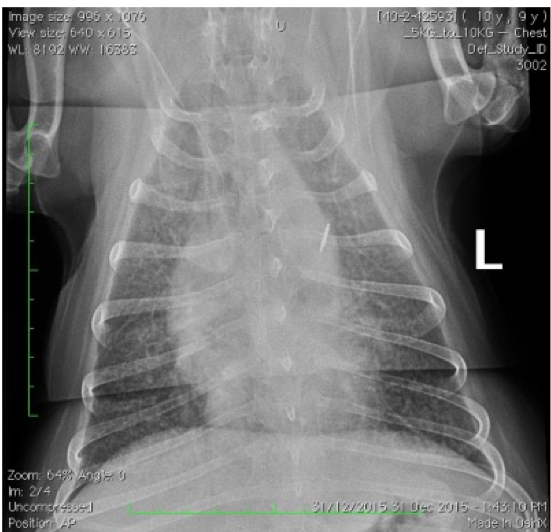

Which lung pattern is shown in Case 1? Justify your answer.

A

Interstitial

There is a diffuse increase in radiodensity (greying-out, lace curtain) but no border obliteration